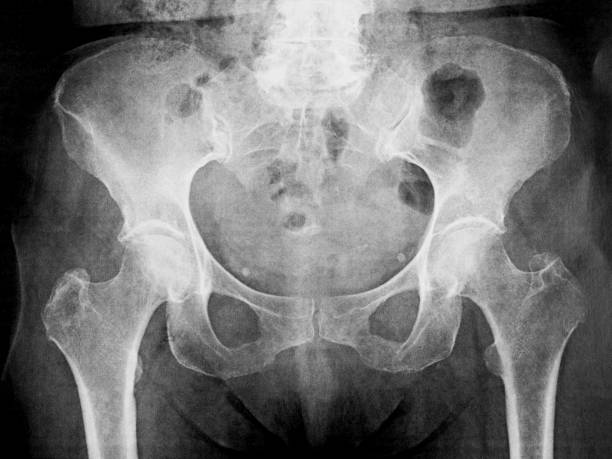

골반은 복부 하단에 위치하고 있는데 양쪽의 2개 볼기뼈와 후단부의 천골(엉치뼈)와 미골(꼬리뼈)로 구성되어 있으며 척추 부분과 하지를 연결하여 체중을 지탱하며 각종 내장과 자궁, 난소, 방광 등 주요 장기를 외부 충격에서 보호할 수 있습니다.

골반 통증 원인 4. 골반 불균형

골반 통증 원인 네 번째는 골반 불균형입니다. 골반을 불균형하게 하는데에도 여러 요인이 있지만 이로 인하여 몸의 균형을 무너뜨리고 여러 신체 이상을 나타나게 할 수 있습니다. 특히 여성의 경우에는 골반이 틀어지면 자궁을 압박하기 때문에 이로 인하여 생리통 혹은 각종 여성질환을 유발할 수 있기 때문에 장기적으로 증상을 완화하기 위해서는 만성으로 자리 잡기 전에 빠른 대응이 필요합니다.